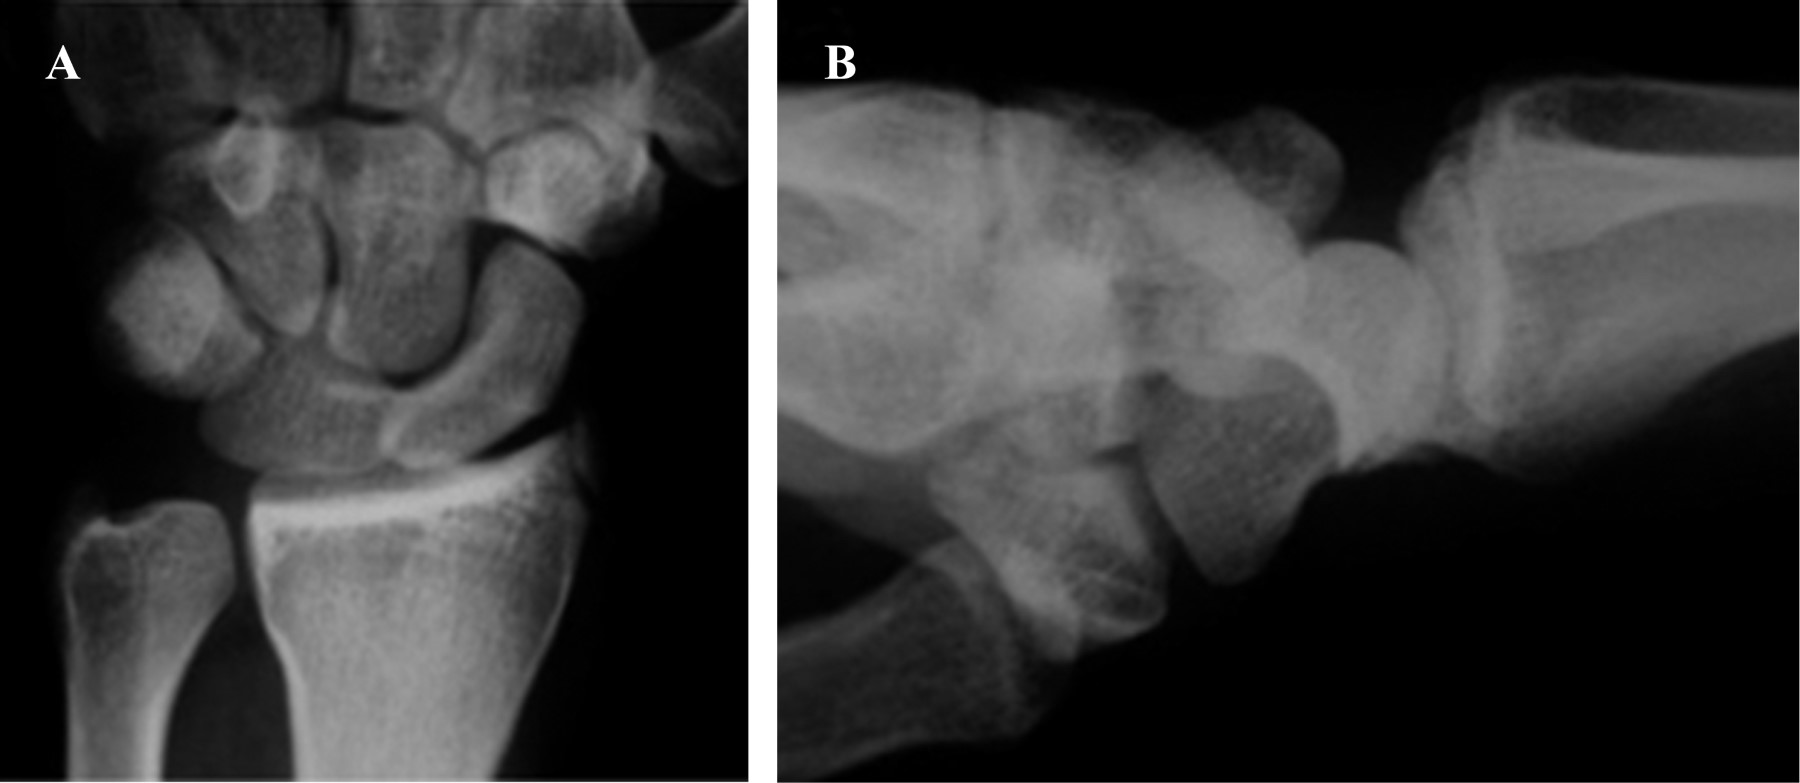

Se define lesión de arco mayor aquélla donde la energía de la lesión afecta estructuras óseas alrededor del semilunar y lesión de arco menor donde la energía progresa alrededor del semilunar, siendo exclusivamente ligamentaria, pudiendo producir luxaciones perilunares o del semilunar10 (Figura 1). Se está introduciendo el término de lesión de arco intermedio a lesiones con afectación tanto ósea como ligamentaria.10 Estas alteran severamente la anatomía y biomecánica normal del carpo. Linscheid y su equipo15 contribuyeron en gran medida a la comprensión de la biomecánica del carpo desarrollando una clasificación para la inestabilidad carpiana. Mayfield y su grupo13 la modificaron definiendo un patrón secuencial de disrupción ligamentaria que resulta en una inestabilidad progresiva perilunar.

Figura 1